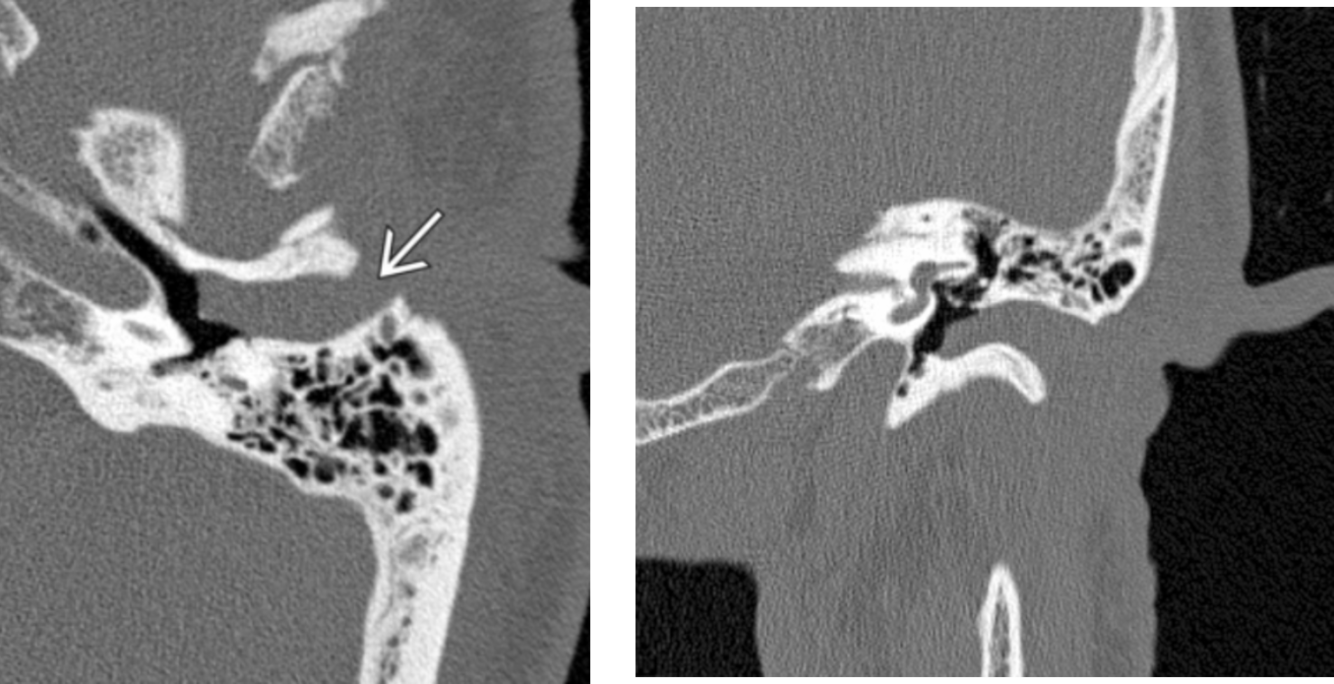

Medial epitympanic congenital cholesteatoma that erodes portions of the ossicles.

Solid arrow: choleastatoma

open arrow: erosion of the long process of the incus and hub of the stapes

Curved arrow: erosion of the lateral bony margin of the tympanic segment of the facial nerve canal

**Tympanic segment of the facial nerve will always be aberrant in the location of the oval window instead of inferior to the lateral semi-circular canal